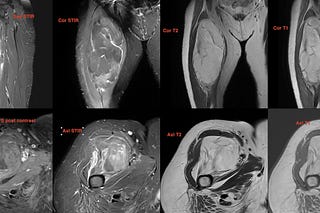

Case of the Day - 091 - 2025 08 26 - How Many Signs of an Intramuscular Schwannoma?

34-years old with pain along the medial and posterior aspects of the proximal leg with a positive Tinel sign.